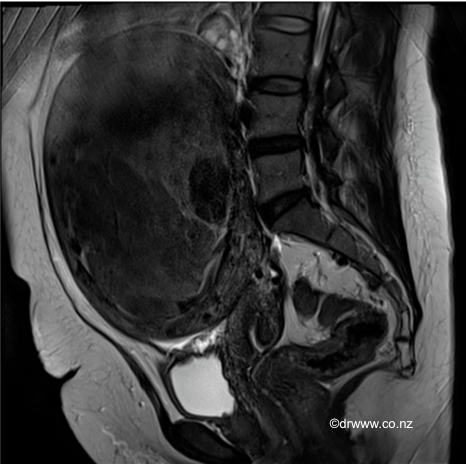

MRI image of a large 15cm fibroid that was managed with a Laparoscopic Myomectomy

• Fibroids may be diagnosed at the time of a pelvic examination, such as a Pap smear. Alternatively, the fibroid may be imaged by ultrasound, CT or MRI. MRI can be beneficial in assessing the location and size of individual fibroids